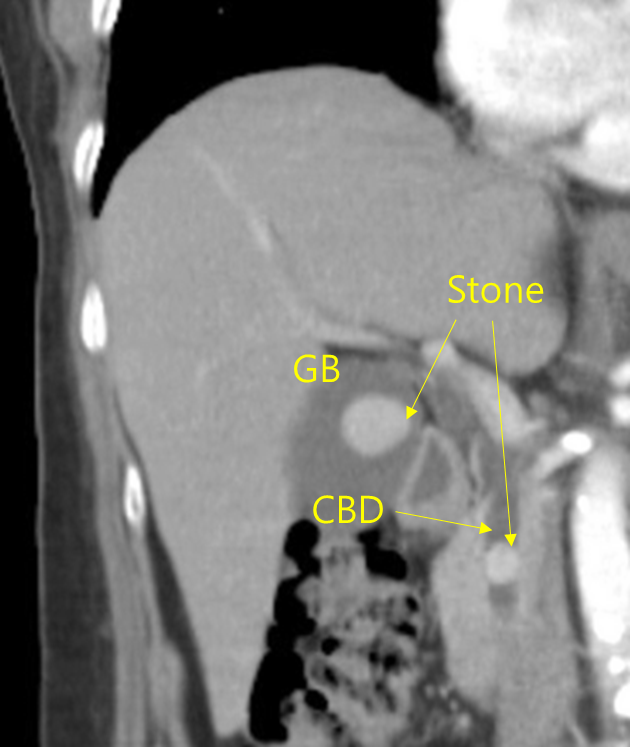

47세 여자가 2일 전부터 오른쪽 윗배가 아파서 병원에 왔다. 혈압 140/90 mmHg, 맥박 90회/분, 호흡 17회/분, 체온 37.8℃ 이다. 오른쪽 윗배에 압통이 있고 반동압통은 없다. 혈액검사 결과는 다음과 같다. 복부 컴퓨터단층촬영 사진이다. 치료는?

혈색소 14.5 g/dL, 백혈구 12,500/mm3, 혈소판 275,000/mm3, 총빌리루빈 6.6 mg/dL, 알칼리인산분해효소 324 U/L, 아스파르테이트아미노전달효소 175U/L, 알라닌아미노전달효소 194U/L

Img | CT: CBD stone, GB stone |

• CT에서 CBD stone이 명확히 관찰되므로 CBD stone에 의한 acute cholangitis로 진단할 수 있다. Biliary colic pain, 발열, 황달은 acute cholangitis의 Charcot triad에 해당한다.